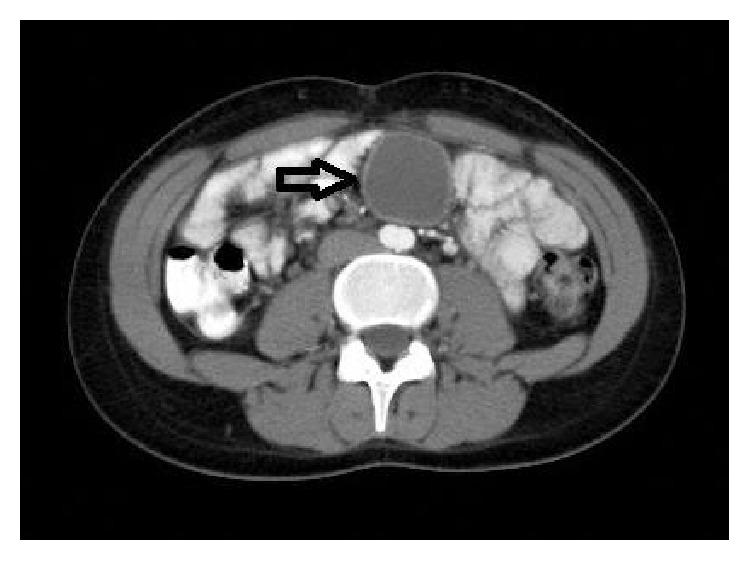

Urachal cyst is an unusual clinical condition, which is usually asymptomatic. In some adult cases, it may lead to complications. The cyst is between umbilicus and urinary bladder. It is diagnosed via ultrasonography and computed tomography. However, in some cases, the diagnosis is made by means of surgical exploration and histopathological evaluation. In this paper, we report a case of a 17-year-old female presenting with painful abdominal mass. At the first evaluation, the case was diagnosed as a mesenteric cyst because the mass located in the mesentery, and final histopathological report revealed the urachal cyst.